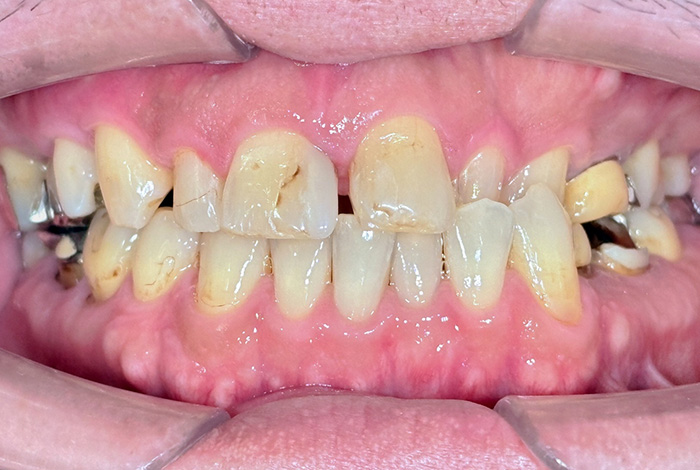

Before

After

患者様は、奥歯でしっかり噛めないことと、前歯の歯並びの乱れを気にされ来院されました。診査の結果、前歯部の叢生(歯並びの乱れ)と、臼歯部の離開咬合(奥歯がしっかり噛み合っていない状態)が認められました。また、臼歯部には古い金属修復物が装着されており、機能面だけでなく審美面においても改善が必要な状態でした。

【治療後】

前歯の歯並びが整い、見た目の改善が認められました。また、奥歯でしっかり噛める状態となり、咬合機能の回復が得られています。

【治療のポイント】

本症例では、歯並びの改善だけでなく、噛み合わせの回復と審美性の向上を同時に行っています。当院は一般歯科と矯正治療の両方に対応しているため、矯正治療後に別の医療機関で補綴治療を行う必要がなく、一貫した治療計画のもとで治療を完結することが可能です。また、奥歯の噛み合わせを矯正治療のみで改善する場合、治療期間が長くなることがありますが、本症例では補綴治療(アンレー)を併用することで、比較的短期間で咬合の改善を行いました。さらに、古い金属修復物をジルコニアに置き換えることで、見た目の改善と機能性の両立を図っています。